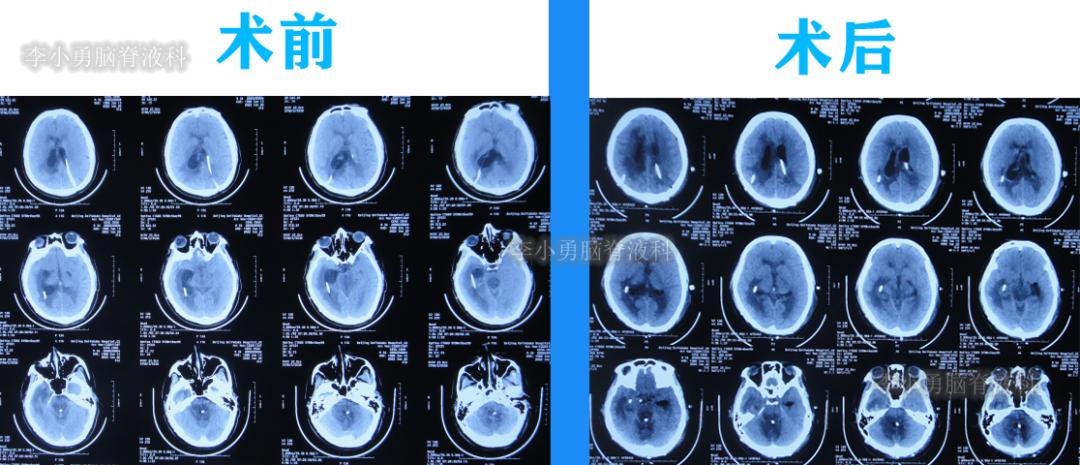

二、第1次在李小勇脑脊液科治疗过程和结果

2020年6月4日(脑囊虫切除术+第三脑室造瘘术后2年5个月,2次脑室腹腔分流术均堵管,期间历经5次住院但脑积水仍反复复发)住入李小勇脑脊液科,入院时:神志朦胧,饮食差,问答有误,自己站立不稳,双眼对视(图-19);既往史:口服抗癫痫药物,青霉素过敏。头颅CT示鞍上占位术后,脑室内可见引流管,脑室系统扩张(图-20)。

图-20:2020年6月4日头颅CT

于2020年10月21日(住院治疗139天),进行了侧脑室和四脑室腹腔分流术。

于2020年10月30日(住院治疗148天),查头颅CT示脑室未见异常(图-32)。

图-32:2020年10月30日头颅CT

2020年11月3日(住院治疗152天)出院,出院时:意识变清,自己站立变稳,能自己走路,双眼对视有好转(图-33)。

图-33:2020年11月3日出院时

三、第2次在李小勇脑脊液科治疗过程和结果

出院后10个月期间患者身体基本正常,生活能自理,但出院后11个月即2021年10月12日,出现嗜睡的症状,在当地的医院查头颅CT示脑室有扩张(图-34)。

2022年4月21日(住院治疗186天),进行了脑室腹腔分流术。

2022年4月28日(住院治疗193天)出院,出院时:意识清楚,言语交流正常,肢体活动、走路基本正常(图-50);查头颅CT示未见异常(图-51)。

图-50:2022年4月28日出院时

图-51:出院时头颅T

四、第3次在李小勇脑脊液科治疗过程和结果

2022年11月15日(李小勇脑脊液科治疗151天)出院,出院时:意识正常,言语交流基本正常,自己走路差点(图-60);头颅CT示未见异常(图-61)。

图-60:2022年11月15日

图-61:出院时头颅CT